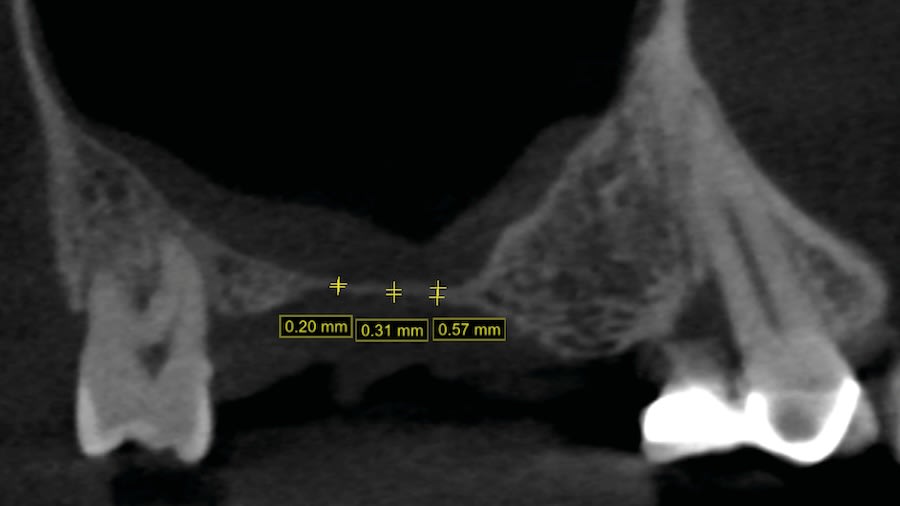

Case 1 (Figure 3 through Figure 24) depicts a 3-year follow-up of combined osseodensification sinus protocol IV in a severely resorbed maxillary ridge with ≤0.5 mm bone height in molar sites and horizontal deficiency at the first premolar site, using a two-stage approach for implant placement.

Step 1: Measure bone height at the osteotomy site on the CBCT. Measure ridge clinical width. A minimum of 7 mm alveolar ridge width is needed. Perform horizontal incision 2 mm to 3 mm palatally from the planned osteotomy site and elevate the flap using regular techniques of the clinician’s choice.

In the posterior maxilla, bone volume, height, and density are often insufficient for implant placement and rehabilitation, which can affect implant long-term stability and success. These anatomical limitations may dictate the need for sinus grafting procedures. Osseodensification is an implant site instrumentation method that enhances bone density and can also be used for transcrestal maxillary sinus augmentation. This technique utilizes bone plasticity through specially designed burs that compact and densify bone along the osteotomy walls while simultaneously propelling bone particles laterally and apically. This process generates a hydrodynamic compaction wave at the bur tip, which propels irrigation fluid into the sinus cavity lifting the membrane and simultaneously compacting bone particles grafting the sinus with autogenous bone. Additionally, the flutes of the osseodensification bur permit the operator to subsequently graft biomaterial, facilitating further elevation of the Schneiderian membrane. Current literature outlines three specific protocols for sinus floor elevation and implant placement utilizing osseodensification with residual bone height (RBH) requirements: ≥6 mm for protocol I, ≥4–5 mm for protocol II, or ≥2–3 mm for protocol III, with concurrent implant placement in the presence of adequate bone and soft-tissue volume. Osseodensification-mediated sinus grafting allows for shorter surgery duration, reduced postoperative edema, less reported pain, and subsequently decreased analgesic intake compared to lateral window techniques. This article details the step-by-step osseodensification sinus lift protocol IV, a two-stage sinus floor elevation indicated in cases of RBH ≤0.5–1.5 mm as an alternative to lateral window techniques.